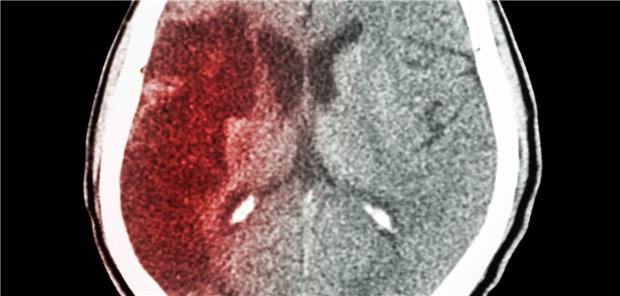

Wurde bei Hypertonikern mit Schlaganfall der Blutdruck rasch gesenkt, reduzierte sich die Reinfarktrate um 56 Prozent.

© stockdevil / Getty Images / iStock

Schlaganfall

Rasche Drucksenkung nützt doch!